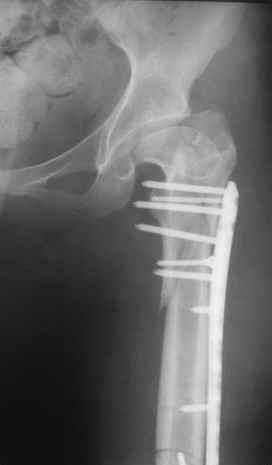

Re: Перелом проксимального отдела диспластичного б

Прошу прощения, со снимками глюк произошел. Высылаю. С уважением Евгений У.